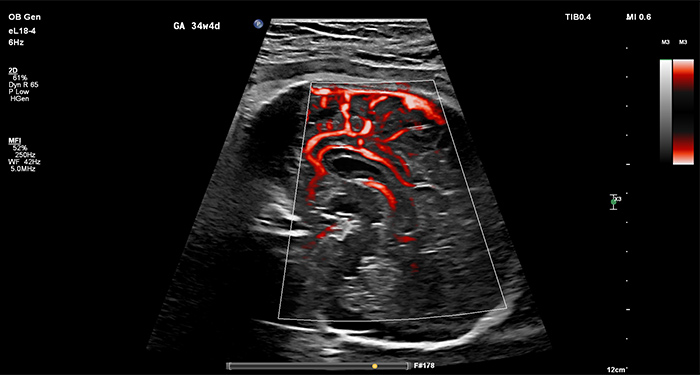

Le mode d’imagerie Philips MicroFlow Imaging (MFI), disponible sur la sonde eL18-4, permet de détecter et d’apprécier des flux sanguins de petit calibre et/oude petite vitesseau niveau des vaisseaux du fœtus, du placenta, de l’utérus et des ovaires. Visionnez la vidéo Sonde Philips eL18-4 avec MicroFlow Imaging (MFI) ci-dessous pour en savoir plus.